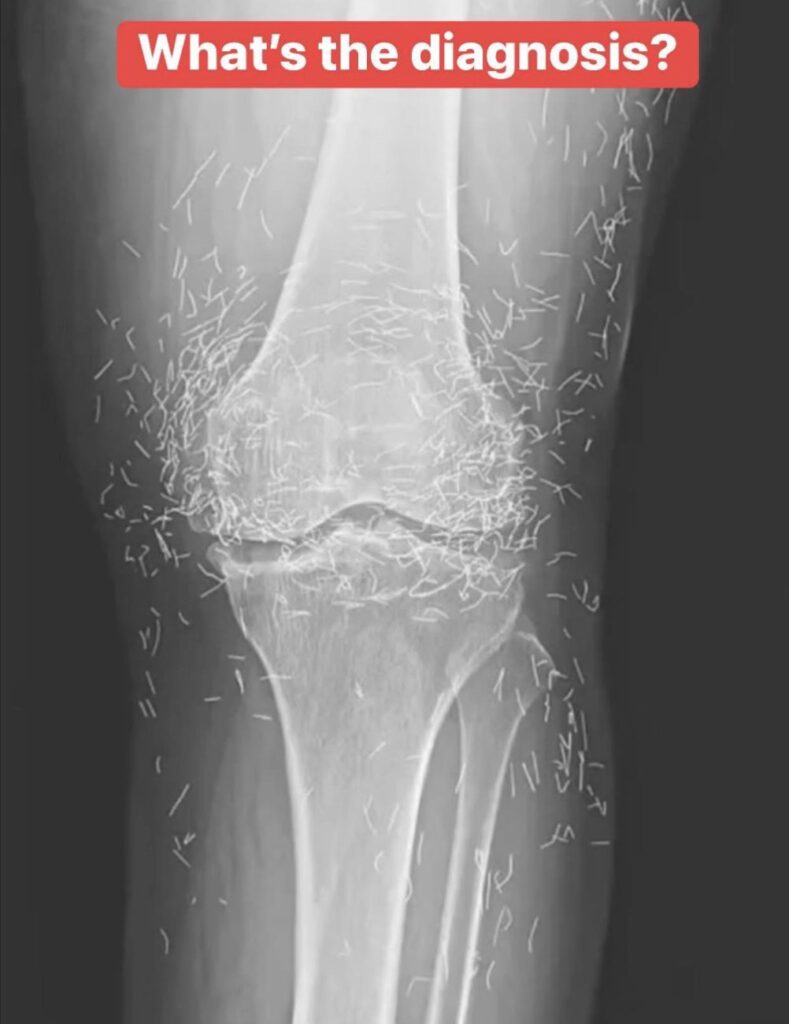

When a 65-year-old South Korean woman went in for knee pain, doctors weren’t expecting to strike gold. But that’s exactly what they found.

So she turned to acupuncture, according to a case published in the New England Journal of Medicine.

Acupuncture, a centuries-old alternative treatment, involves inserting needles into the body at specific points to relieve pain or treat illnesses. In this case, the needles— presumably made of gold — were intentionally left in her knees for continued stimulation.

He also warned that embedded needles can complicate X-ray readings. “The needles may obscure some of the anatomy,” Guermazi said in 2013.

The New England Journal of Medicine

Even more concerning, needles left in the body can make future medical imaging dangerous. “The patient can’t go into an MRI because needles left in the body may move, and damage an artery,” Guermazi added.